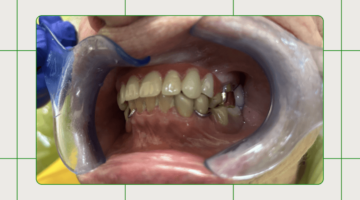

Case study image before after

Case Study: Comprehensive Restorative Care with Veneers, Crowns, and Implants